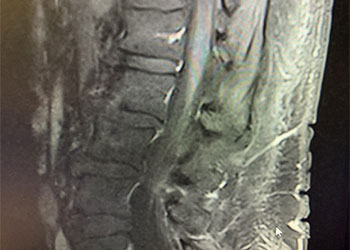

The patient is a 65-year-old woman with a history of hypertension and hypercholesterolemia who was experiencing bilateral lower extremity weakness and numbness for close to one year in addition to some urinary incontinence for the preceding 6 months. The patient ultimately saw a neurologist who ordered an MRI of her lumbar sacral region revealing a bright signal within the lower spinal cord on T2-weighted sequences with enhancement and flow voids seen on the dorsal aspect of the spinal cord suggestive of spinal dural arteriovenous fistula (Figure 1). She was referred for a neurovascular consultation. Physical examination was significant for 4/5 weakness on the right hip and leg muscle groups with decreased pinprick and light touch sensation in both lower extremities in a stocking distribution and decreased vibratory sensation in both toes.

(Figure 1) Pre-treatment MRI image of lumbar sacral region.